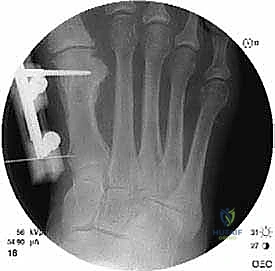

2. التقييم الشعاعي (Radiographic Evaluation)

تعتبر الأشعة السينية (X-rays) حجر الزاوية في التخطيط لعملية شيفرون البعيدة. يطلب الدكتور هطيف صور أشعة بوضعيات محددة (أمامية خلفية، وجانبية) أثناء وقوف المريض وتحميل وزن جسمه على قدميه (Weight-bearing X-rays). هذا أمر بالغ الأهمية لأن التشوه يظهر بحجمه الحقيقي فقط تحت تأثير وزن الجسم.

من خلال هذه الصور، يقوم الدكتور هطيف بقياس زوايا حاسمة تحدد نوع الجراحة المطلوبة:

* زاوية إبهام القدم الأروح (Hallux Valgus Angle - HVA): هي الزاوية بين المحور الطولي لعظم المشط الأول والمحور الطولي للسلامية الدانية. الزاوية الطبيعية أقل من 15 درجة. في الحالات الخفيفة إلى المتوسطة (التي تناسبها عملية شيفرون)، تتراوح بين 15 إلى 40 درجة.

* الزاوية بين أمشاط القدم (Intermetatarsal Angle - IMA): هي الزاوية بين المحور الطولي لعظم المشط الأول وعظم المشط الثاني. الزاوية الطبيعية أقل من 9 درجات. عملية شيفرون البعيدة مثالية عندما تكون هذه الزاوية بين 9 و 15 درجة.

* تقييم مفصل (DMAA - Distal Metatarsal Articular Angle): لتقييم ميلان السطح المفصلي.

* موقع العظام السمسمية: تقييم مدى انزياحها عن مسارها الطبيعي.

* وجود التهاب مفاصل تنكسي (خشونة): فحص تآكل الغضاريف، حيث أن وجود خشونة شديدة قد يغير خطة العلاج من عملية شيفرون إلى عملية دمج المفصل (Arthrodesis).